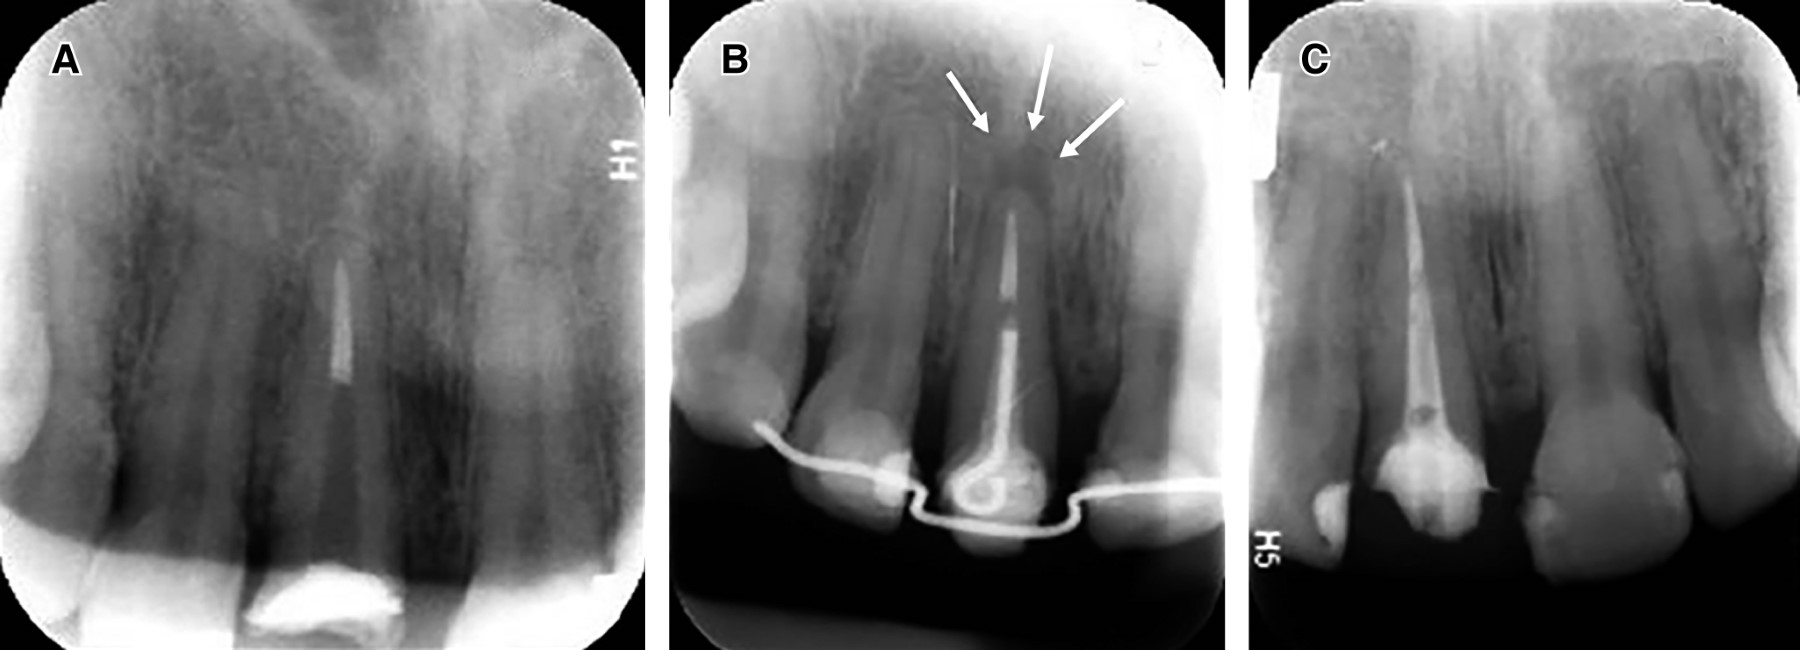

Una vez concluido este proceso, se realizó el cambio de cadenas elastoméricas de segunda generación con un periodo semanal. Al cumplir la tercera semana, se observó el contacto del loop con el alambre de ortodoncia, cumpliendo con el objetivo de los 3 mm de extrusión necesarios (Figura 3). Se tomó una radiografía de control donde se pudo constatar la migración en sentido coronal de dicho órgano dentario (Figura 4).

Se efectuaron citas de control posteriores al presente procedimiento. Una vez transcurrida la primera semana se descartó presencia de signos de infección o inflamación y se refirió al departamento de restauradora para la colocación del núcleo y provisional (Figura 6). A los siete meses, se tomó una radiografía periapical y se comparó radiografías del proceso de antes, durante (a las tres semanas) y después (a los siete meses). Se observó la aposición o formación del tejido óseo en el área del ápice (Figura 7).

Figura 4

Figura 7